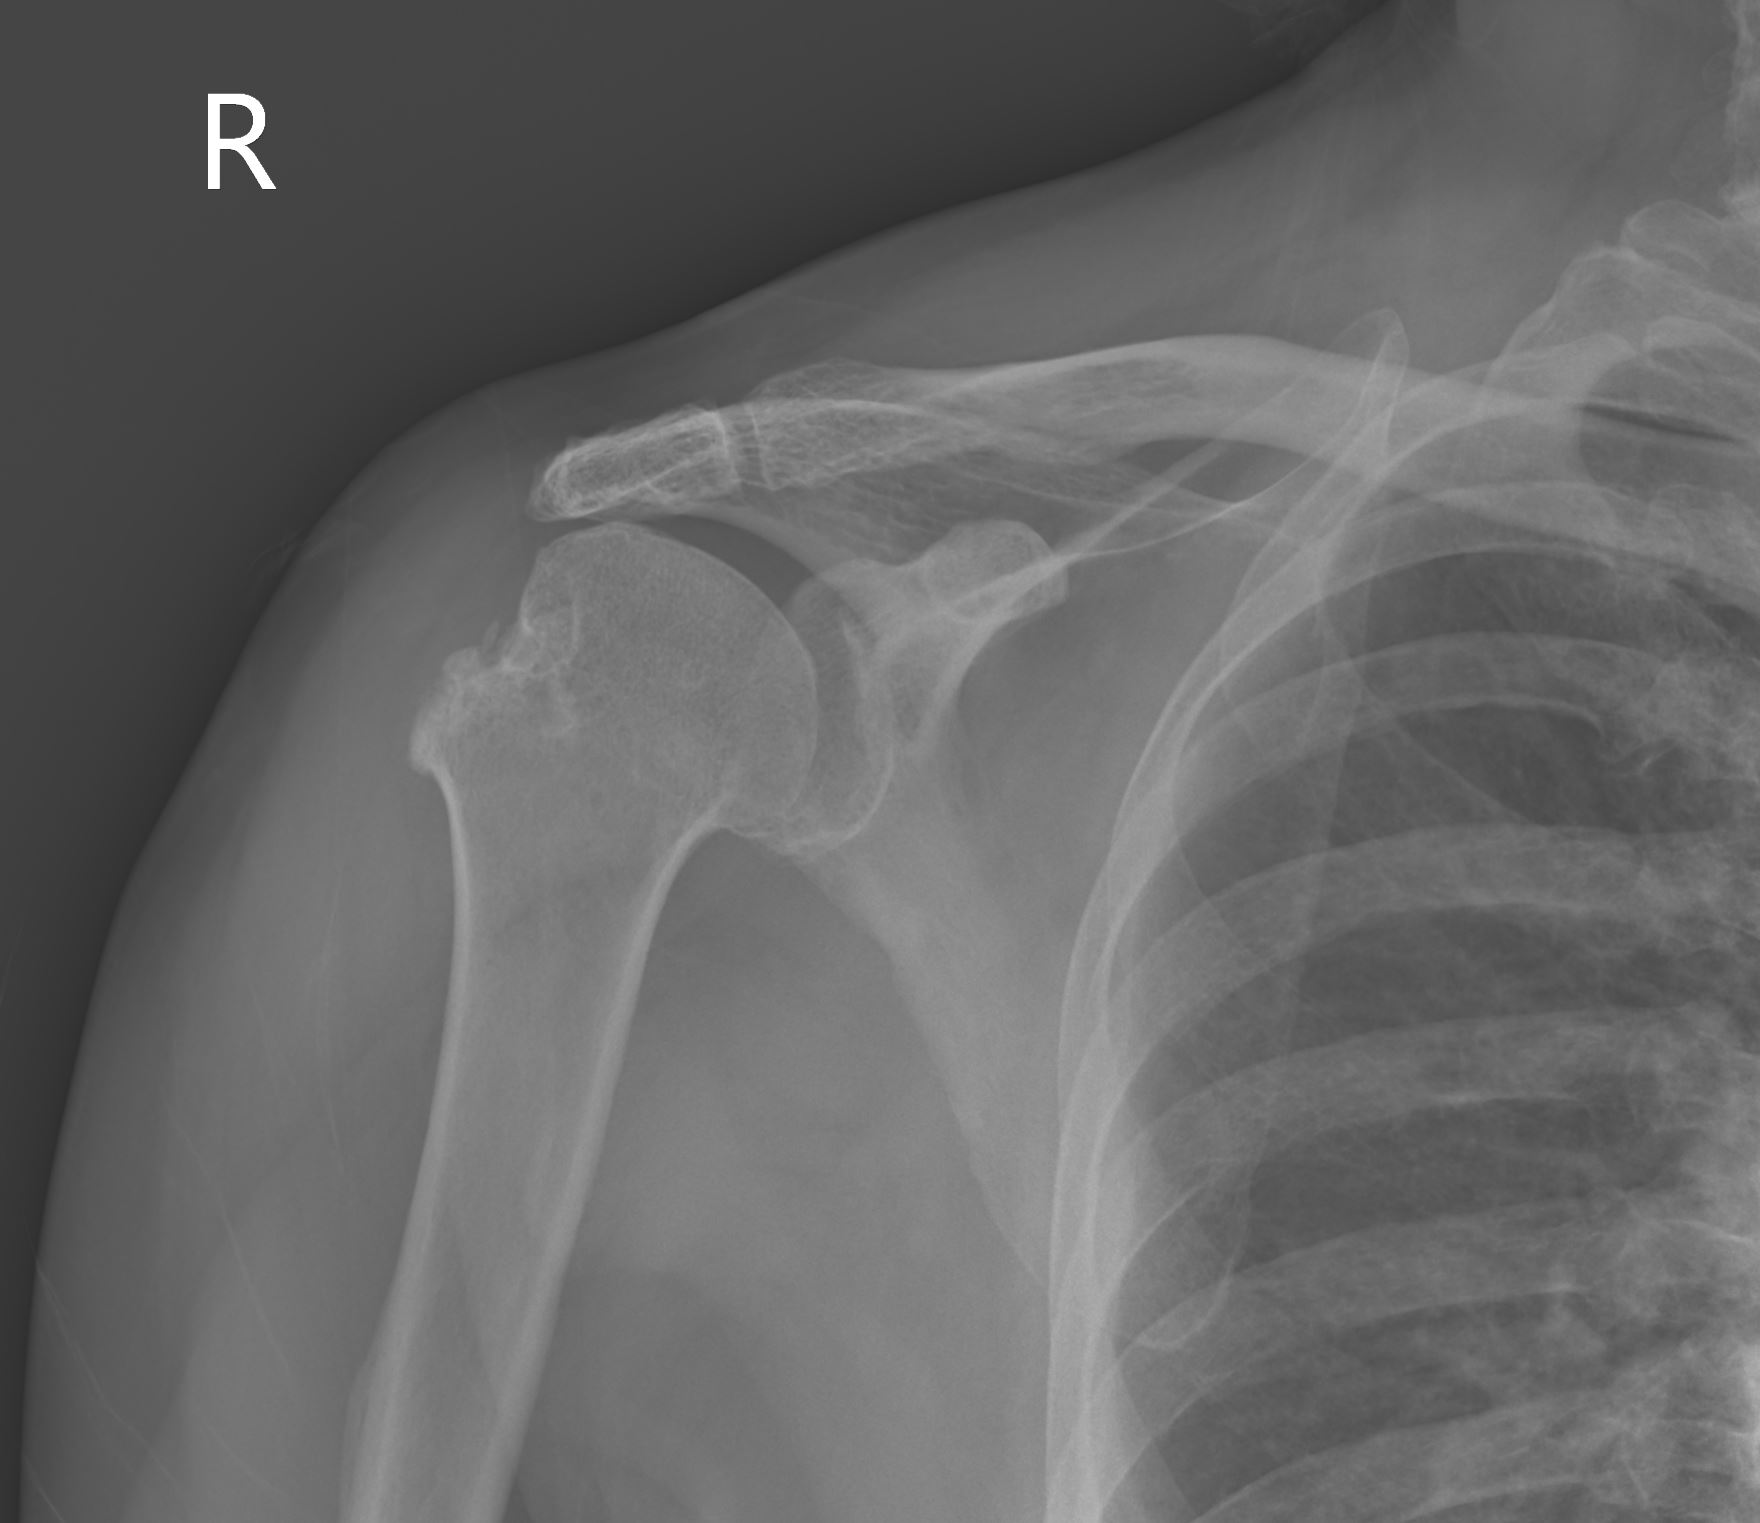

個案70歲女性,跌倒撐地後右肩疼痛無法動,圖片1的X光可見右肩關節前脫位。我們先執行鎖骨上臂神經叢阻斷術(影片1),然後由肩棘部下方進行橫向掃描,記錄前脫位復位前的影像 (圖片2、影片2),在患者疼痛大幅減少後進行徒手復位,復位後會立即執行超音波的確認(圖片3、影片3),最後三角巾固定後追蹤復位後的X光(圖片4)。

圖片470歲女性右肩關節前脫位復位後以三角巾固定之肩部X光